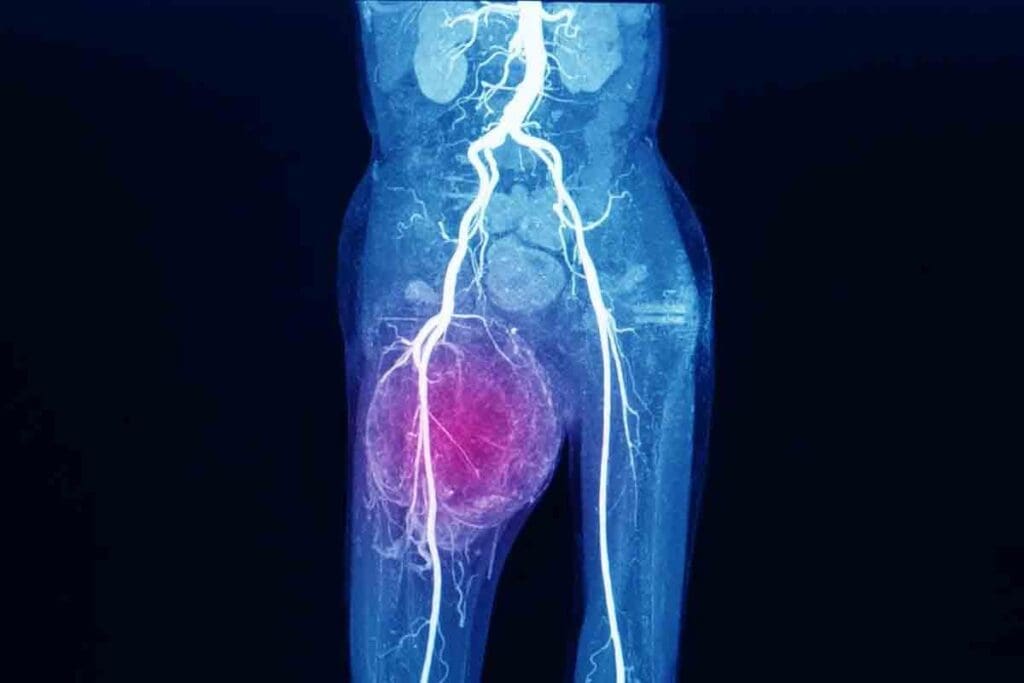

Symptom 7: Vascular Compression Effects

A sarcoma calf can compress blood vessels, causing changes in the limb. This compression leads to various symptoms that are important to notice.

Swelling and Edema

Swelling and edema are common effects of vascular compression. When blood vessels are compressed, blood flow is blocked. This leads to fluid buildup in tissues.

Key signs to look out for include:

- Persistent swelling that doesn’t improve with elevation or rest

- Edema that is accompanied by pain or discomfort

Changes in Skin Color and Temperature

Vascular compression can also change skin color and temperature. Reduced blood flow makes the skin cooler to the touch.

Notable changes may include:

- Skin that appears pale or cyanotic due to reduced oxygenation

- A noticeable difference in temperature between the affected and unaffected limbs

Circulation Problems and Their Significance

Circulation problems from vascular compression are serious. It’s important to watch for these symptoms closely.

Ignoring circulation issues can lead to severe complications. Understanding these symptoms is key for timely medical help.

“Early detection of vascular compression effects can significantly impact the management and treatment of sarcoma patients.” – Medical Expert